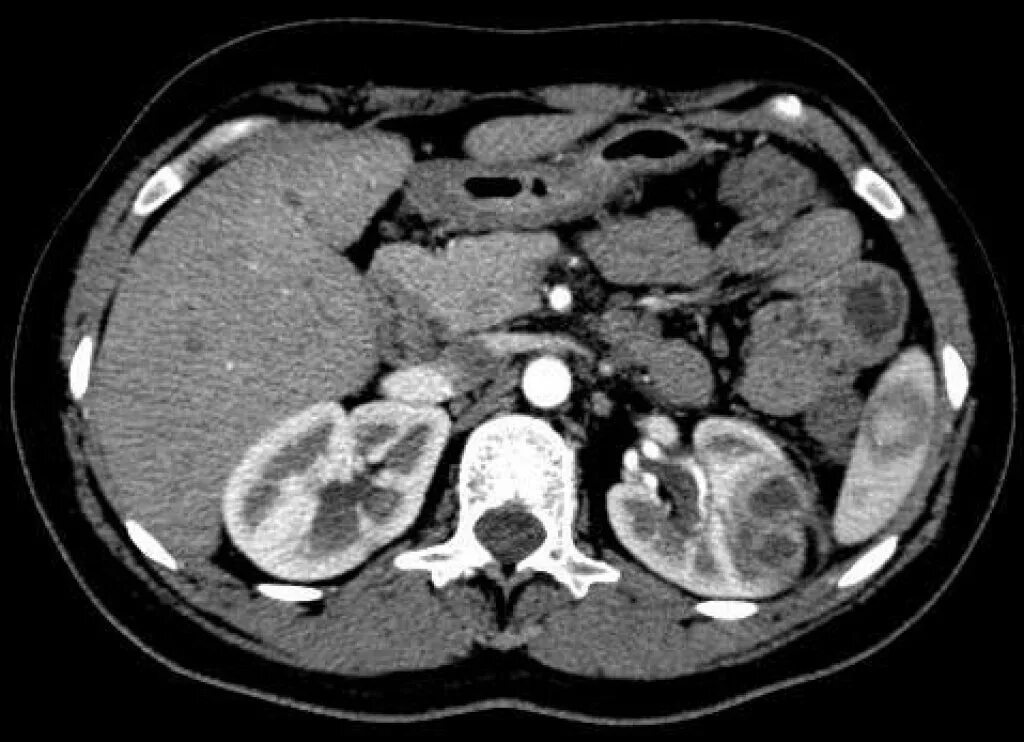

Болит кт